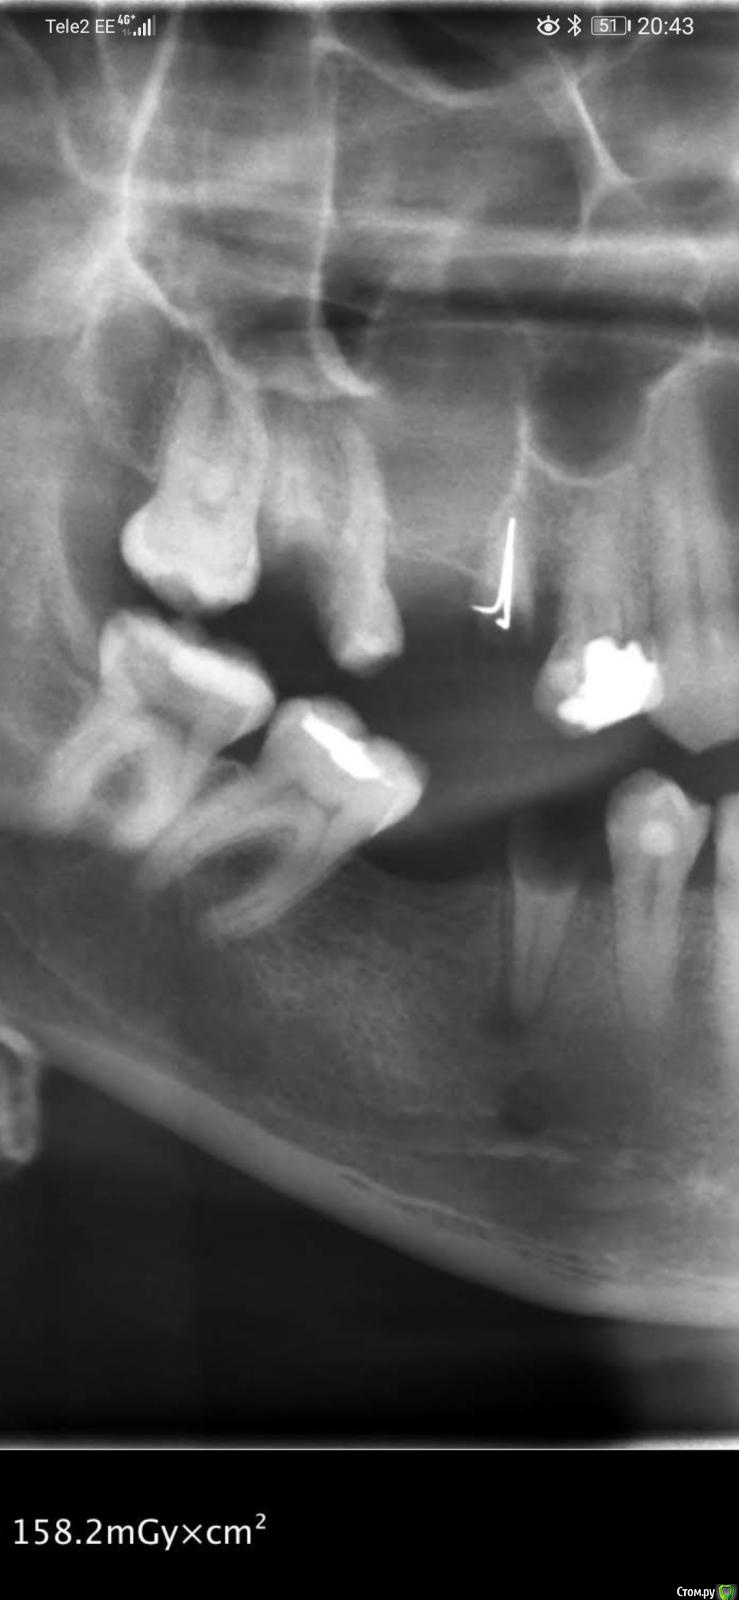

32worldwide Опубликовано 1 июня, 2020 Поделиться Опубликовано 1 июня, 2020 (изменено) Мне кажется сдесь одонтогенная киста. На телефоне есть ещё один его снимок 2010 года. Да, спрашиваю потому что не знаю что делать с ним дальше.. Могу отправить в центр ЧЛХ. Состояние пациента отличное, отака и жалоб нет после дренировпния и удаления двух корней. Поэтому встаёт вопрос а надо ли что то делать или может нужно понаблюдать 6 месяцев и сделать повторно КЛКТ?32, вам лучше было бы создать свою тему, но как-то вопросы типа "убирать дренаж или нет" говорят о том что вы немного не понимаете что делать. Снимок неинформативный но я бы имел онконастороженность.Мне кажется сдесь одонтогенная киста. На телефоне есть ещё один его снимок 2010 года. Да я спрашиваю потому что не знаю что делать с ним дальше.. Могу отправить в центр ЧЛХ. Состояние пациента отличное, отака и жалоб нет после дренировпния и удаления двух корней. Поэтому встаёт вопрос а надо ли что то делать или может нужно понаблюдать 6 месяцев и сделать повторно КЛКТ? Изменено 1 июня, 2020 пользователем 32worldwide Ссылка на комментарий

32worldwide Опубликовано 2 июня, 2020 Поделиться Опубликовано 2 июня, 2020 Вот скрины с 3Д. Там видна тень от дренирующей трубки. Вопрос такой же кто как порекомендует вести пациента дальше. И есть отправить на ЧЛХ то что там будут делать(интересно просто)? Ссылка на комментарий